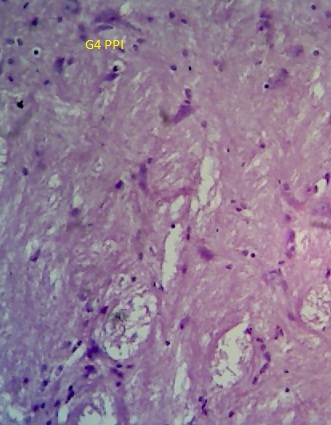

The error in the image in fig. 9 in the published research article has occurred from our side due to the magnification variation and oversight while placing the same in our article which was submitted for publication in your reputed journal. The error is unintentional and due to multiple experiments compilation for the said promising research.

“The image of “G5 PPI group” in fig. 9 is incorrect in the original figure. A corrected fig. is shown below.”

Brain

Fig. 9: Photomicrograph of sections of brain and liver of animals of control group and animals administered with a single dose of 250 mg/kg to PEGylated G4 and G5 PPI dendrimers after 24 h. (magnification: 400X)